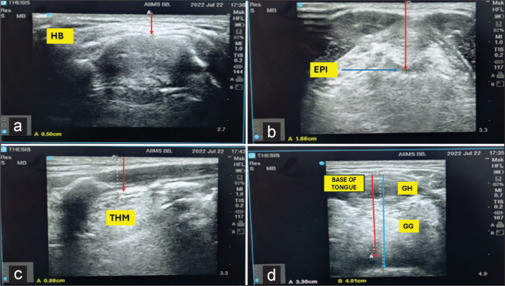

Methods: This prospective observational study enroled 120 patients posted for elective surgery under general anaesthesia, without anticipated difficult airways. The skin to hyoid bone distance (SHBD), skin to epiglottis distance (SED), skin to thyrohyoid membrane distance (STHMD), and TTOHR were measured on USG. Modified Cormack-Lehane (CL) grading at laryngoscopy was the primary outcome. Statistical analysis included ROC curve analysis, multivariable logistic regression, and evaluation of predictive models combining multiple USG parameters.

Results: The incidence of difficult laryngoscopy and intubation was 11.6% and 6.6%, respectively. The highest diagnostic performance was observed for SED, with an area under the curve (AUC) of 0.95 [95% confidence interval (CI): 0.91, 0.98], a cut-off value of 1.87 cm, a sensitivity of 100%, a specificity of 89%, and a diagnostic accuracy of 90%. STHMD followed with an AUC of 0.94 (95% CI: 0.88, 0.99), a cut-off of 1.58 cm, a sensitivity of 90%, a specificity of 86%, and a diagnostic accuracy of 84%. TTOHR showed an AUC of 0.92 (95% CI: 0.78, 1.00), with a cut-off value of 0.80, a sensitivity of 92%, a specificity of 98%, and the highest diagnostic accuracy of 97% (95% CI: 0.96, 1.00). Various models, tested using three or four parameters, showed AUC values ranging from 0.96 to 0.97. A model containing TTOHR, SHBD, and STHMD was identified as a best-fit model for predicting difficult laryngoscopy.